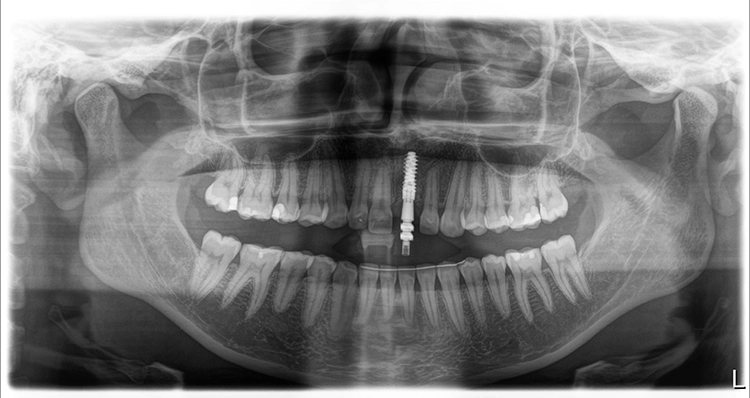

In Vorbereitung auf die Implantatplanung und das CAD/CAM-Herstellen der temporären Krone erfolgte eine digitale Datenerfassung mit dem Intraoralscanner (Trios 3, 3Shape). Der Datensatz der Ausgangssituation sollte später bei der CAD-Konstruktion hilfreiche Informationen liefern (Abb. 3). Mit dem Scan ist die Ausgangssituation digital archiviert und steht jederzeit zum Abruf bereit. Zudem wurde ein DVT für die Planung der Implantatposition am dreidimensionalen Bild vorgenommen und der DICOM-Datensatz in die Implantatplanungssoftware importiert (Abb. 4 und 5).

Theoretisch kann in der Planungssoftware der STL-Datensatz aus dem Intraoralscanner (Ausgangssituation oder Set-up) hinzugezogen und so die Implantatposition aus prothetischer Sicht ideal definiert werden. Im vorgestellten Fall ergab die 3D-Diagnostik ein ausreichend stabiles Knochenvolumen in regio 21. Geplant worden ist die Insertion eines BLX-Implantates (Straumann).